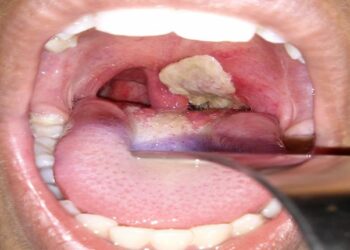

Diphtheria Kills 520 Children In Kano

The Director - General of Kano State Primary Healthcare Management Board, Dr Muhammad Mahmud says about 520 children are ...